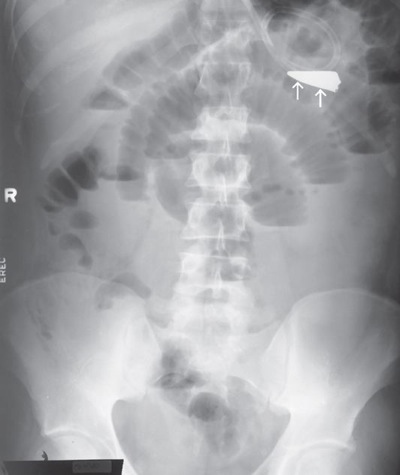

What position is demonstrated?

Left Lateral Decubitus Abdomen